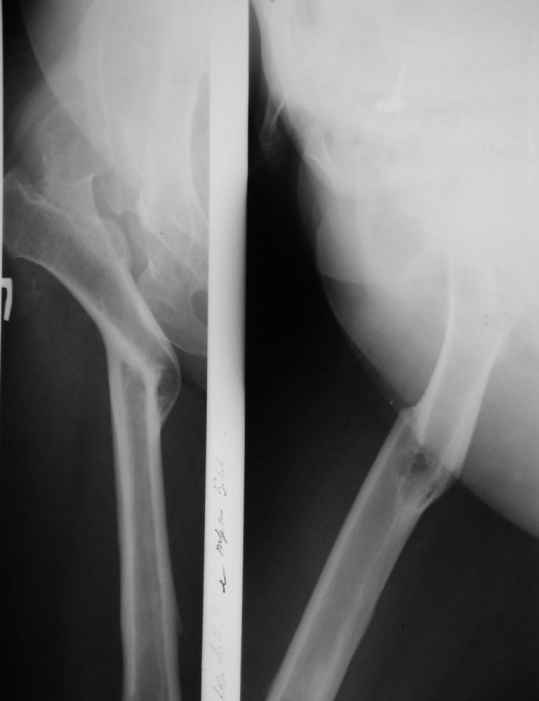

-Клиновидная остеотомия бедра на вершине деформации, с углом открыты внутрь. Это позволит выпрямить бедро, добиться полной адаптации обоих фрагментов. Использование ножки Вагнера не позволит фиксировать проксимальный отломок и потребуется какая то дополнительная фиксация, возможно пластиной.

-То же самое с использованием ножки Helios (Biomed) позволит выполнить вполне качественный остеосинтез (ножка из двух частей и позволяет оптиально зафиксировать оба фрагмента), к тому же с возможностью блокирования. Поэтому дополнительной фиксации не потребуется.

-Во всех наших наблюдениях применялась чашка Цвеймюллера.